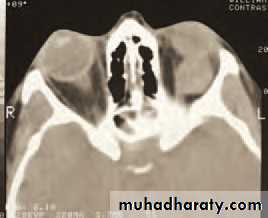

• An MRI or CT scan is helpful in diagnosis and in planning treatment (Fig. 4.2). The condition usually responds to intravenous broad spectrum antibiotics. It may be necessary to drain an abscess or decompress the orbit particularly if the optic nerve is compromised. Optic nerve function must be closely watched, monitoring acuity, colour vision and testing for a relative afferent pupillary defect. Orbital decompression is usually performed with the help of an ENT specialist.

• Fig. 4.2 (a) The clinical appearance of a patient with right orbital cellulitis.

• (b) A CT scan showing a left opaque ethmoid sinus and subperiosteal orbital abscess.